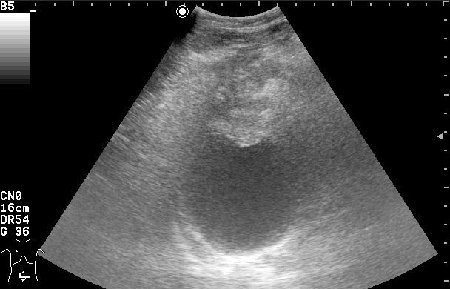

УЗИ - Воспаление урахуса

Женщина 42 лет с болями внизу живота, дизурическими явлениями, повышением температуры.

Сонограммы мочевого пузыря

, в случае обнаружения образования в области верхушки мочевого пузыря, я должна думать о патологии урахуса.

Похоже на опухоль, но по анамнезу я больше склоняюсь к воспалению урахуса!

Согласна с первым постом-возможно нагноение урахуса(и клиника подходит)